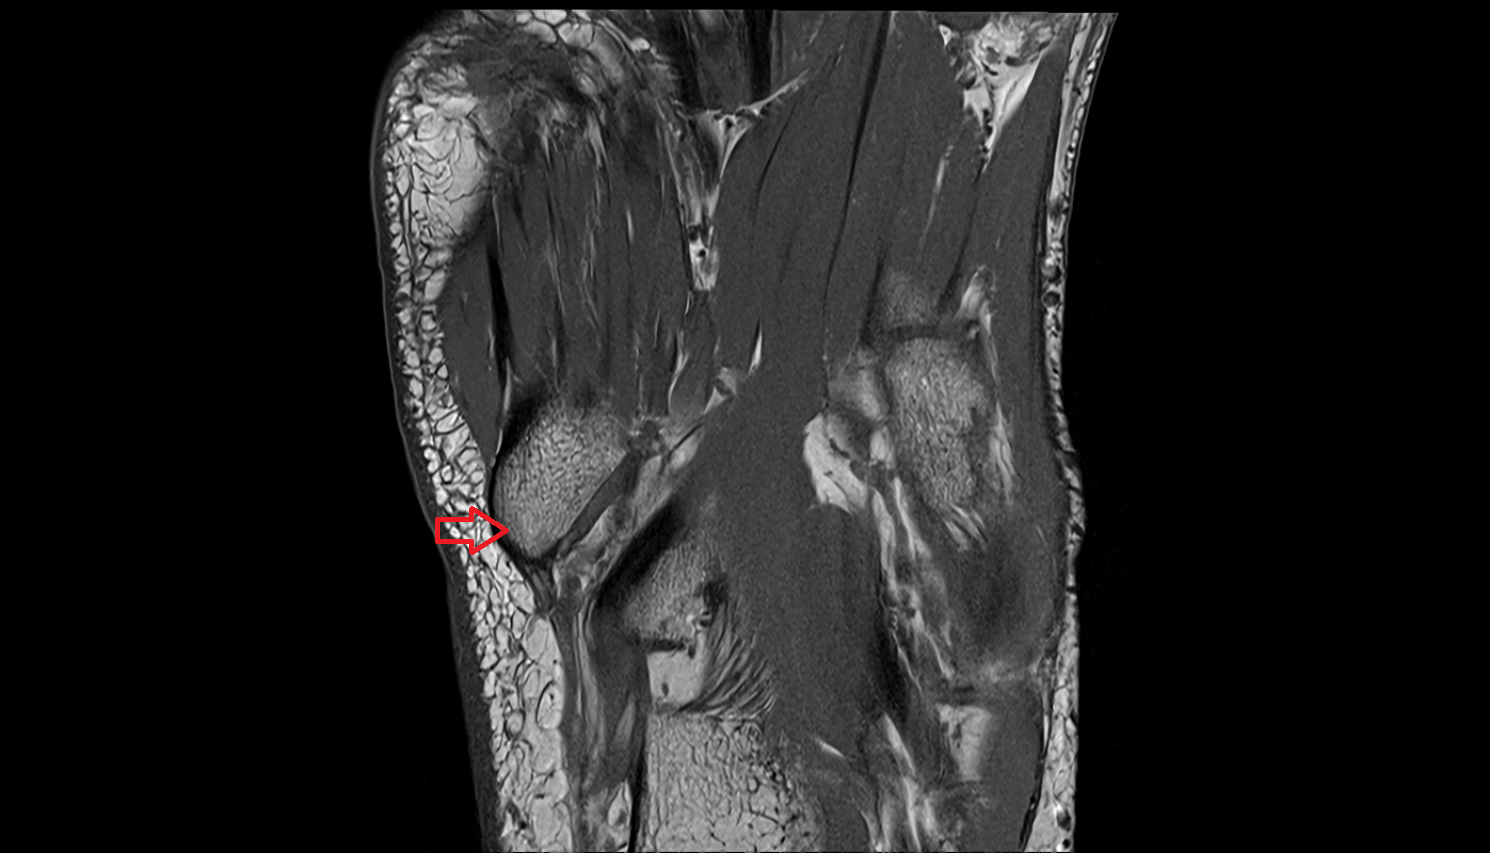

- Calcaneus

- Anterior process of calcaneus

- Sustentaculum tali

- Tuberosity of navicular bone

- Cuboid

- Ankle joint

- Talocalcaneal joint

- Talocalcaneonavicular joint

- Calcaneocuboid joint

- Navicular bone